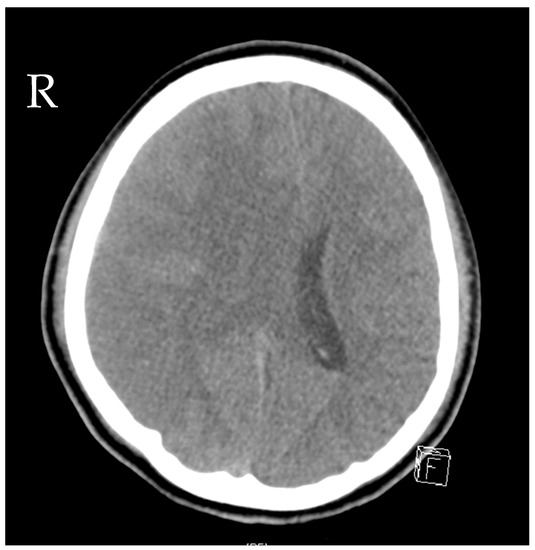

Source control was also conducted: the initial LD was removed, and a new EVD was inserted due to ongoing high ICP (combination of hydrocephalus e vacuo and malresorptivus). See Figure 4 for the corresponding computed tomography. Therapy success was measured through microbiology cure: The cerebrospinal fluid (CSF) culture became negative after 7 days of C/T treatment, and the CSF cell count decreased. The neurological status improved rapidly as a sign of clinical therapy success, and the CRP and leucocytes decreased rapidly, as shown in Figure 3. Another 10 days later, the definitive treatment of hydrocephalus could be obtained with a ventriculoatrial catheter. By the time of hospital discharge, the patient was awake and able to move all four extremities.

Figure 4.

Computed tomography of the head showing distinctive hydrocephalus with pronounced enlargement of the ventricular system (malresorptivus and e-vacuo components).